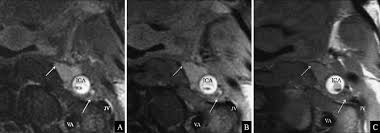

Carotid artery dissection (concept id: Each common carotid artery has an internal and an external branch. Carotid artery dissection is a tear in one of the layers of the artery wall. Spontaneous dissection of the carotid artery occurs in 3 per 100,000 of the population annually (1). It manifests with headache, neck pain, temporary vision loss, and/or ischemic stroke. This causes bleeding into the artery wall. Commonest in those in their mid 40s but seen at any age. Roller coasters are also a no no. Blood vessel walls normally have three layers, and a tear in any of these can allow blood to flow into the resulting space, causing the vessel to bulge. The first portion of each carotid artery is the called the common carotid artery. Carotid artery dissection is a major cause of cerebral infarction in the young. Mr signal of the mural hematoma has a similar temporal evolution than intracerebral counterpart. A carotid dissection can be due to injury.

The natural history of cerebrovascular fmd is unknown and management of symptomatic patients can be challenging. A carotid dissection is a tear in the inner layer of the wall of a carotid artery that allows bleeding into the artery wall. Internal carotid artery (ica) dissection, like arterial dissection elsewhere, is a result of blood entering the media through a tear in the intima 1 and is a common cause of stroke in younger patients. Carotid artery dissection has been described after chiropractic manipulation. It can involve a carotid or vertebral artery and sometimes multiple arteries can be involved.